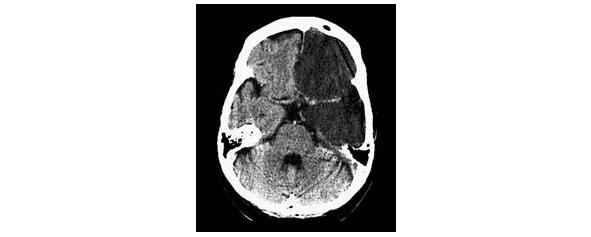

Среди геморрагических вариантов ОНМК выделяют: паренхиматозное кровоизлияние, вентрикулярное кровоизлияние, паренхиматозно-вентрикулярное кровоизлияние (рис. 3), а также субарахноидальное кровоизлияние.

Рисунок 3. КТ-картина паренхиматозно-вентрикулярного кровоизлияния